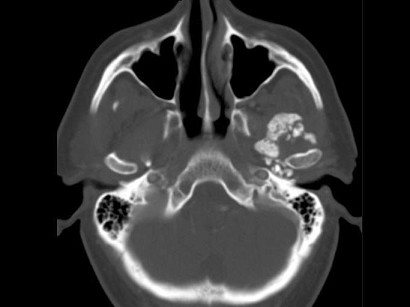

男,60岁,张口受限半年,CT检查如图所示,正确的描述或诊断是()

A.左侧颞颌关节周围软组织内见较多致密钙化影

B.左侧颞颌关节软组织未见肿胀

C.左侧颞颌关节面(颞骨面)骨质增生明显

D.左侧颞颌关节滑膜骨软骨瘤病

E.颞颌关节功能紊乱